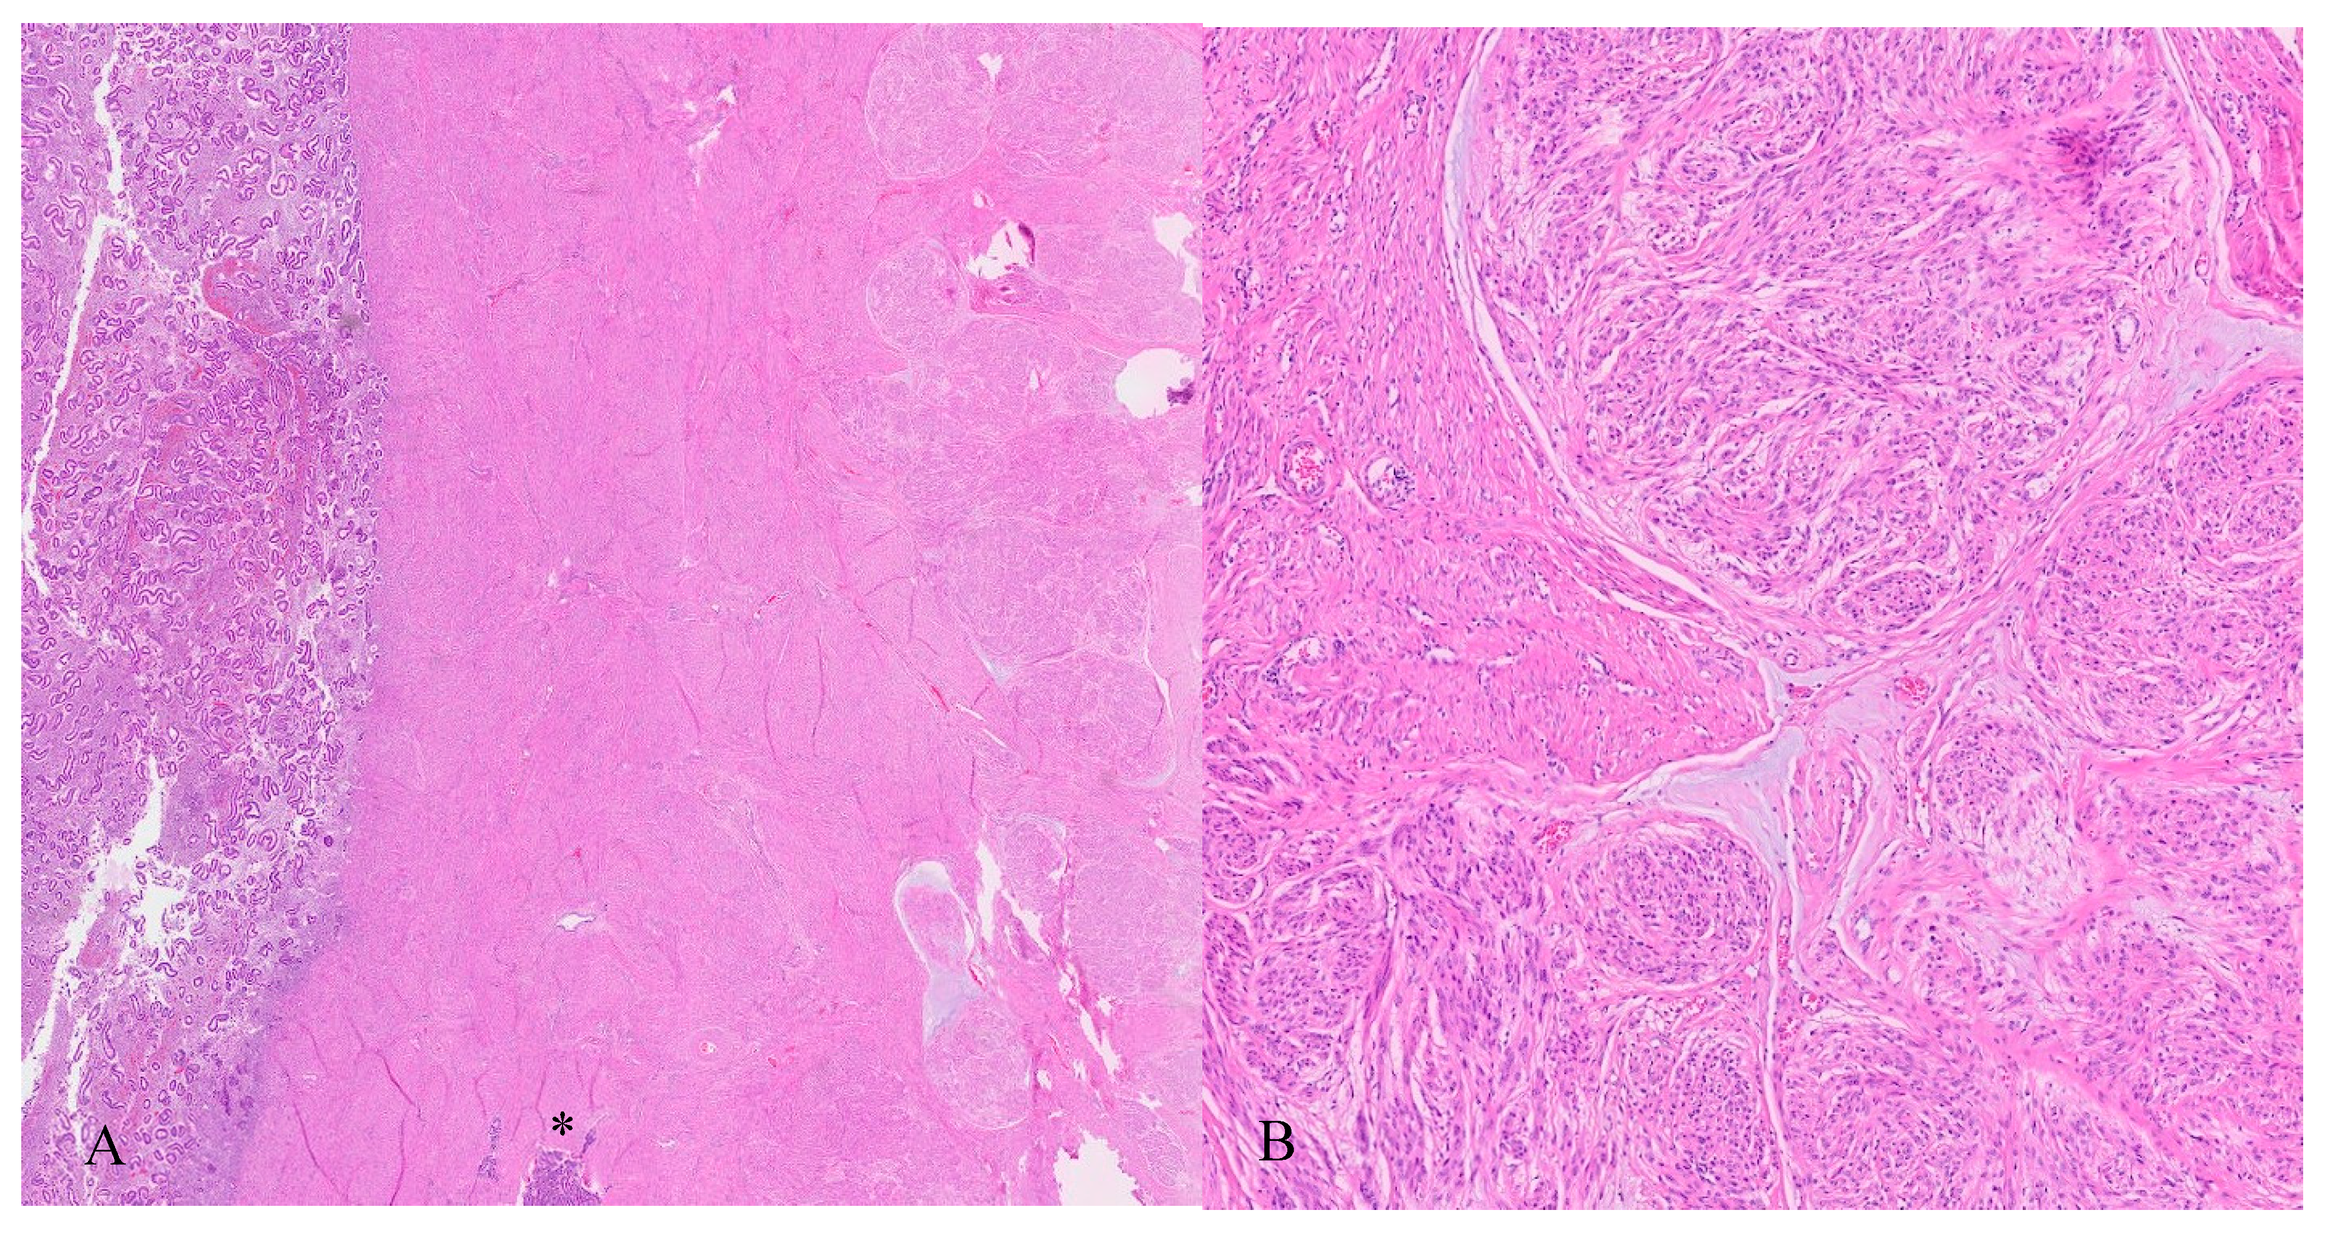

3. Histopathology